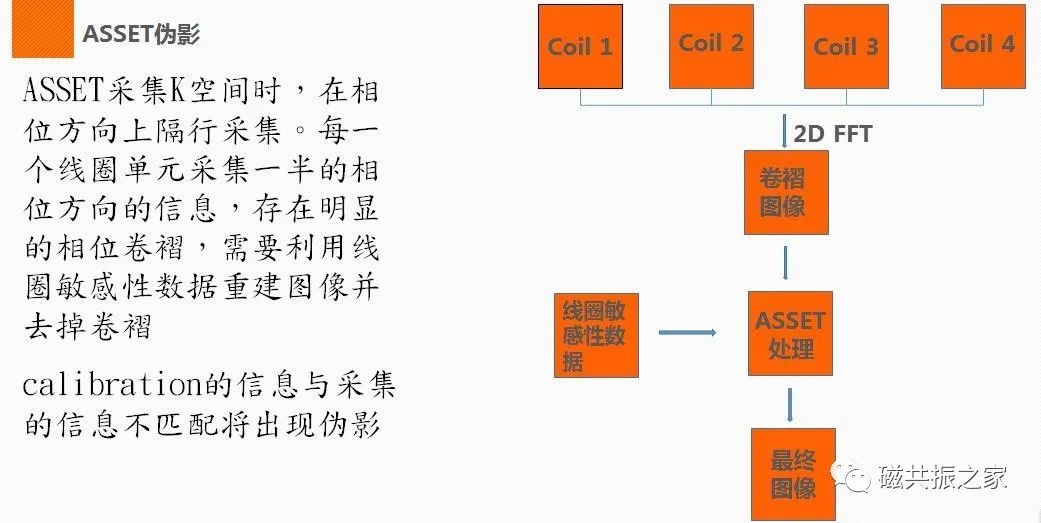

并行采集伪影

并行采集原理如下图:

产生的该伪影的原因:扫描呼吸时相不一致;扫描FOV或Phase FOV选择太小;校准错误等。